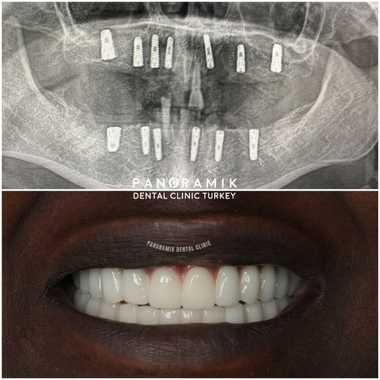

Full Mouth Implants

• Smile Time: Your smile will last for years with your teeth that have been used carefully and carefully and whose controls have not been interrupted. Take a look at our Before and after pictures.